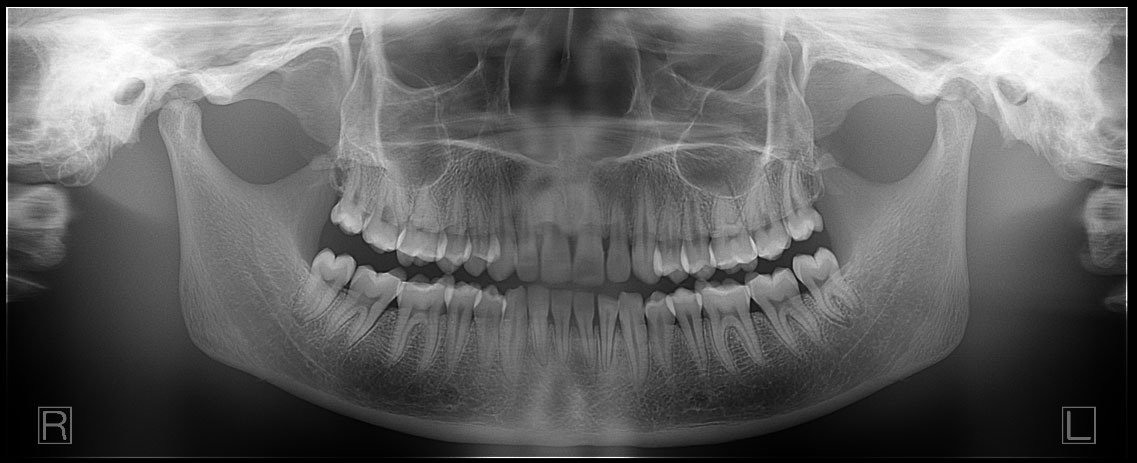

First, it operates as a traditional dental panoramic x-ray machine that creates a panoramic radiograph. This is used by the dentist for general exams, as well as third molar, pediatric and extraoral bitewing exams.

Cephalometric x-ray images are most commonly needed for orthodontic treatment. However, they can also be used for TMJ assessment, sinus evaluation and trauma to the jaw or skull. A cephalometric scan captures both lateral and poster-anterior (PA) images of the entire skull, and these scans are most commonly used as part of orthodontic treatment to measure relative movement of anatomical landmarks.

A somewhat unique characteristic that many dental professionals look for in their cephalometric images is the ability to see soft tissue. Specifically, they use the image to review the relationship a patient’s jaws and teeth have to their soft tissues and the entirety of their skull.